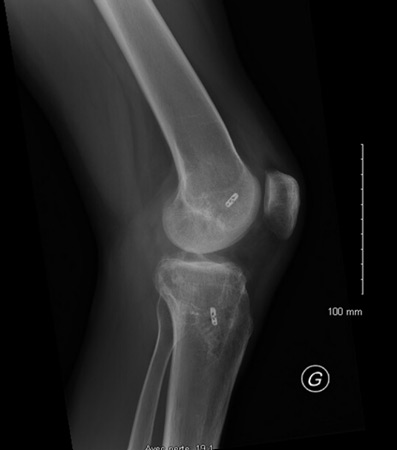

- Knee X-ray: No fractures or bony avulsion

- Knee MRI Findings:

- Rupture of the PCL, PLC and LCL

- Intact ACL

- No meniscal tear

- No cartilage injury